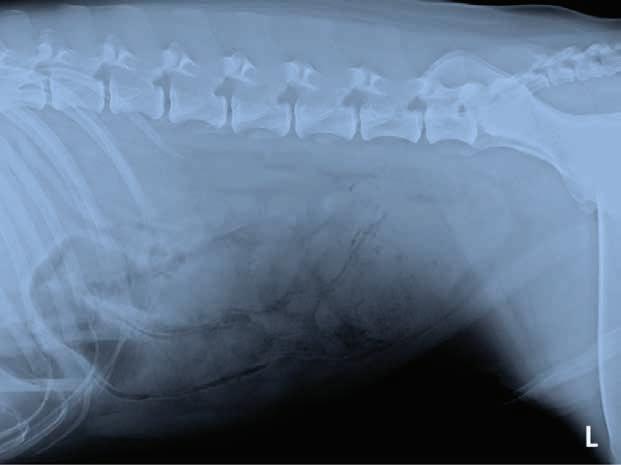

A 3-year-old, male neutered Labrador Retriever presented for chronic diarrhoea. t he patient had a history of inflammatory bowel disease and had undergone multiple previous surgeries for foreign body removal. A colopexy had also been previously performed. t he patient had completed a course of metronidazole on the day of presentation and was also receiving vitamin B12, psyllium husk (metamucil) and probiotics. He was up to date with de-worming treatment and core vaccinations. A three-view abdominal radiograph series was taken as part of the diagnostic workup, and two cropped projections are provided below (Figure 1).

Figure 1. l eft lateral (a) and ventrodorsal (b) abdonimal radiographics of a dog with chronic diarrhoea.

a b